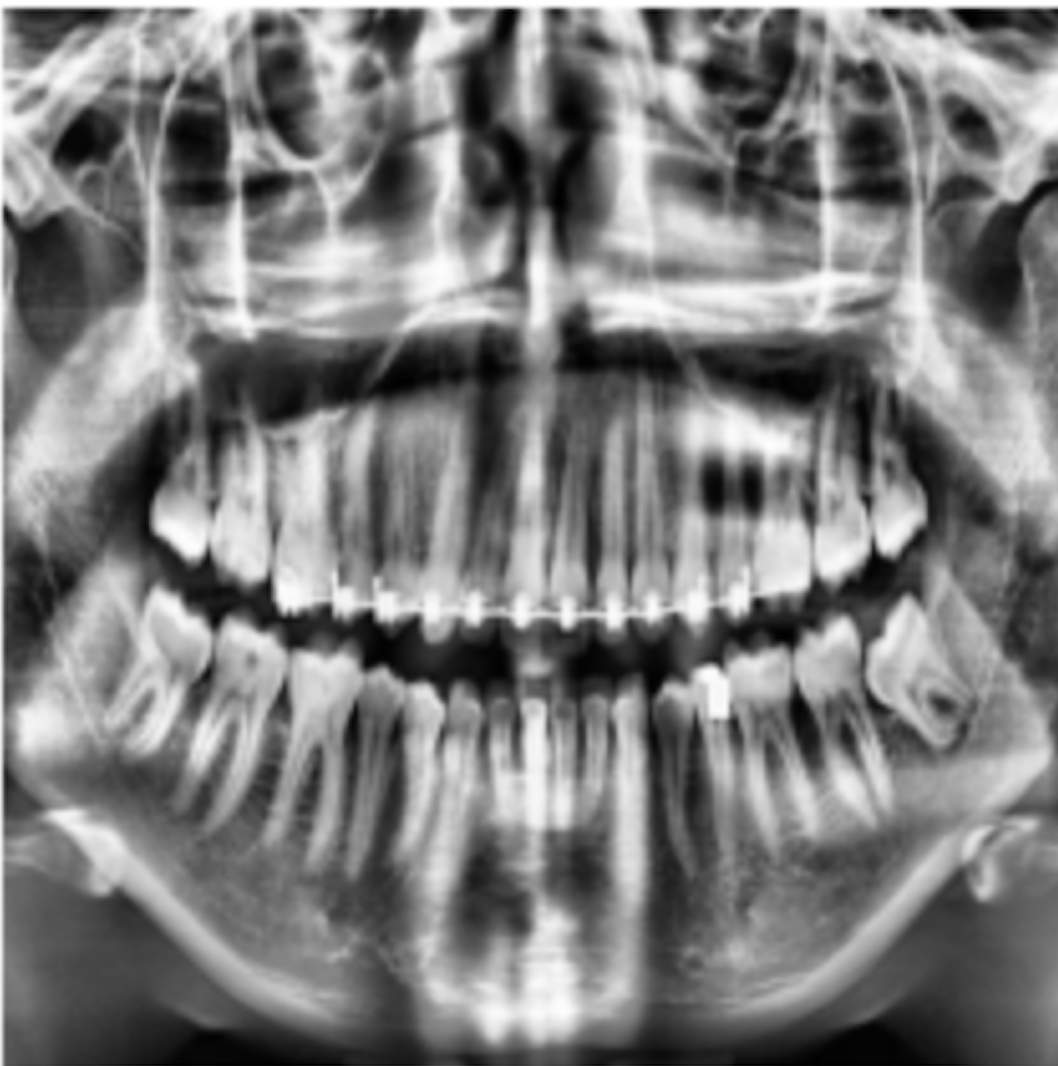

Due to the lack of image labels necessary for training models in the presented dataset, we initially labelled 425 images from the set. We collected two sets of basic annotations, for instance segmentation and object detection respectively. We selected these 425 images randomly from all categories and maintained same distribution of images across all categories as in the original dataset. For manual labelling, we chose the semi-automated annotation tool Roboflow [28] for bounding box annotations needed for the objection detection task. We also used another annotation tool, Apeer [29], to help us create individual segmentation masks for each of the 32 teeth in the images in the dataset. These binary masks provided additional information by focusing on the fine contours and boundaries of the teeth. We converted the resulting segmented polygons into binary maps of size 512×\times512×\times32. This comprehensive approach to annotation was pivotal in ensuring our model’s success in dental image analysis. An example of annotations is shown in Fig. 2.

Refer to caption

Figure 2: (a) Annotated polygon mask. (b) Annotated bounding Box scan. (c) Binary mask of polygon-based annotation